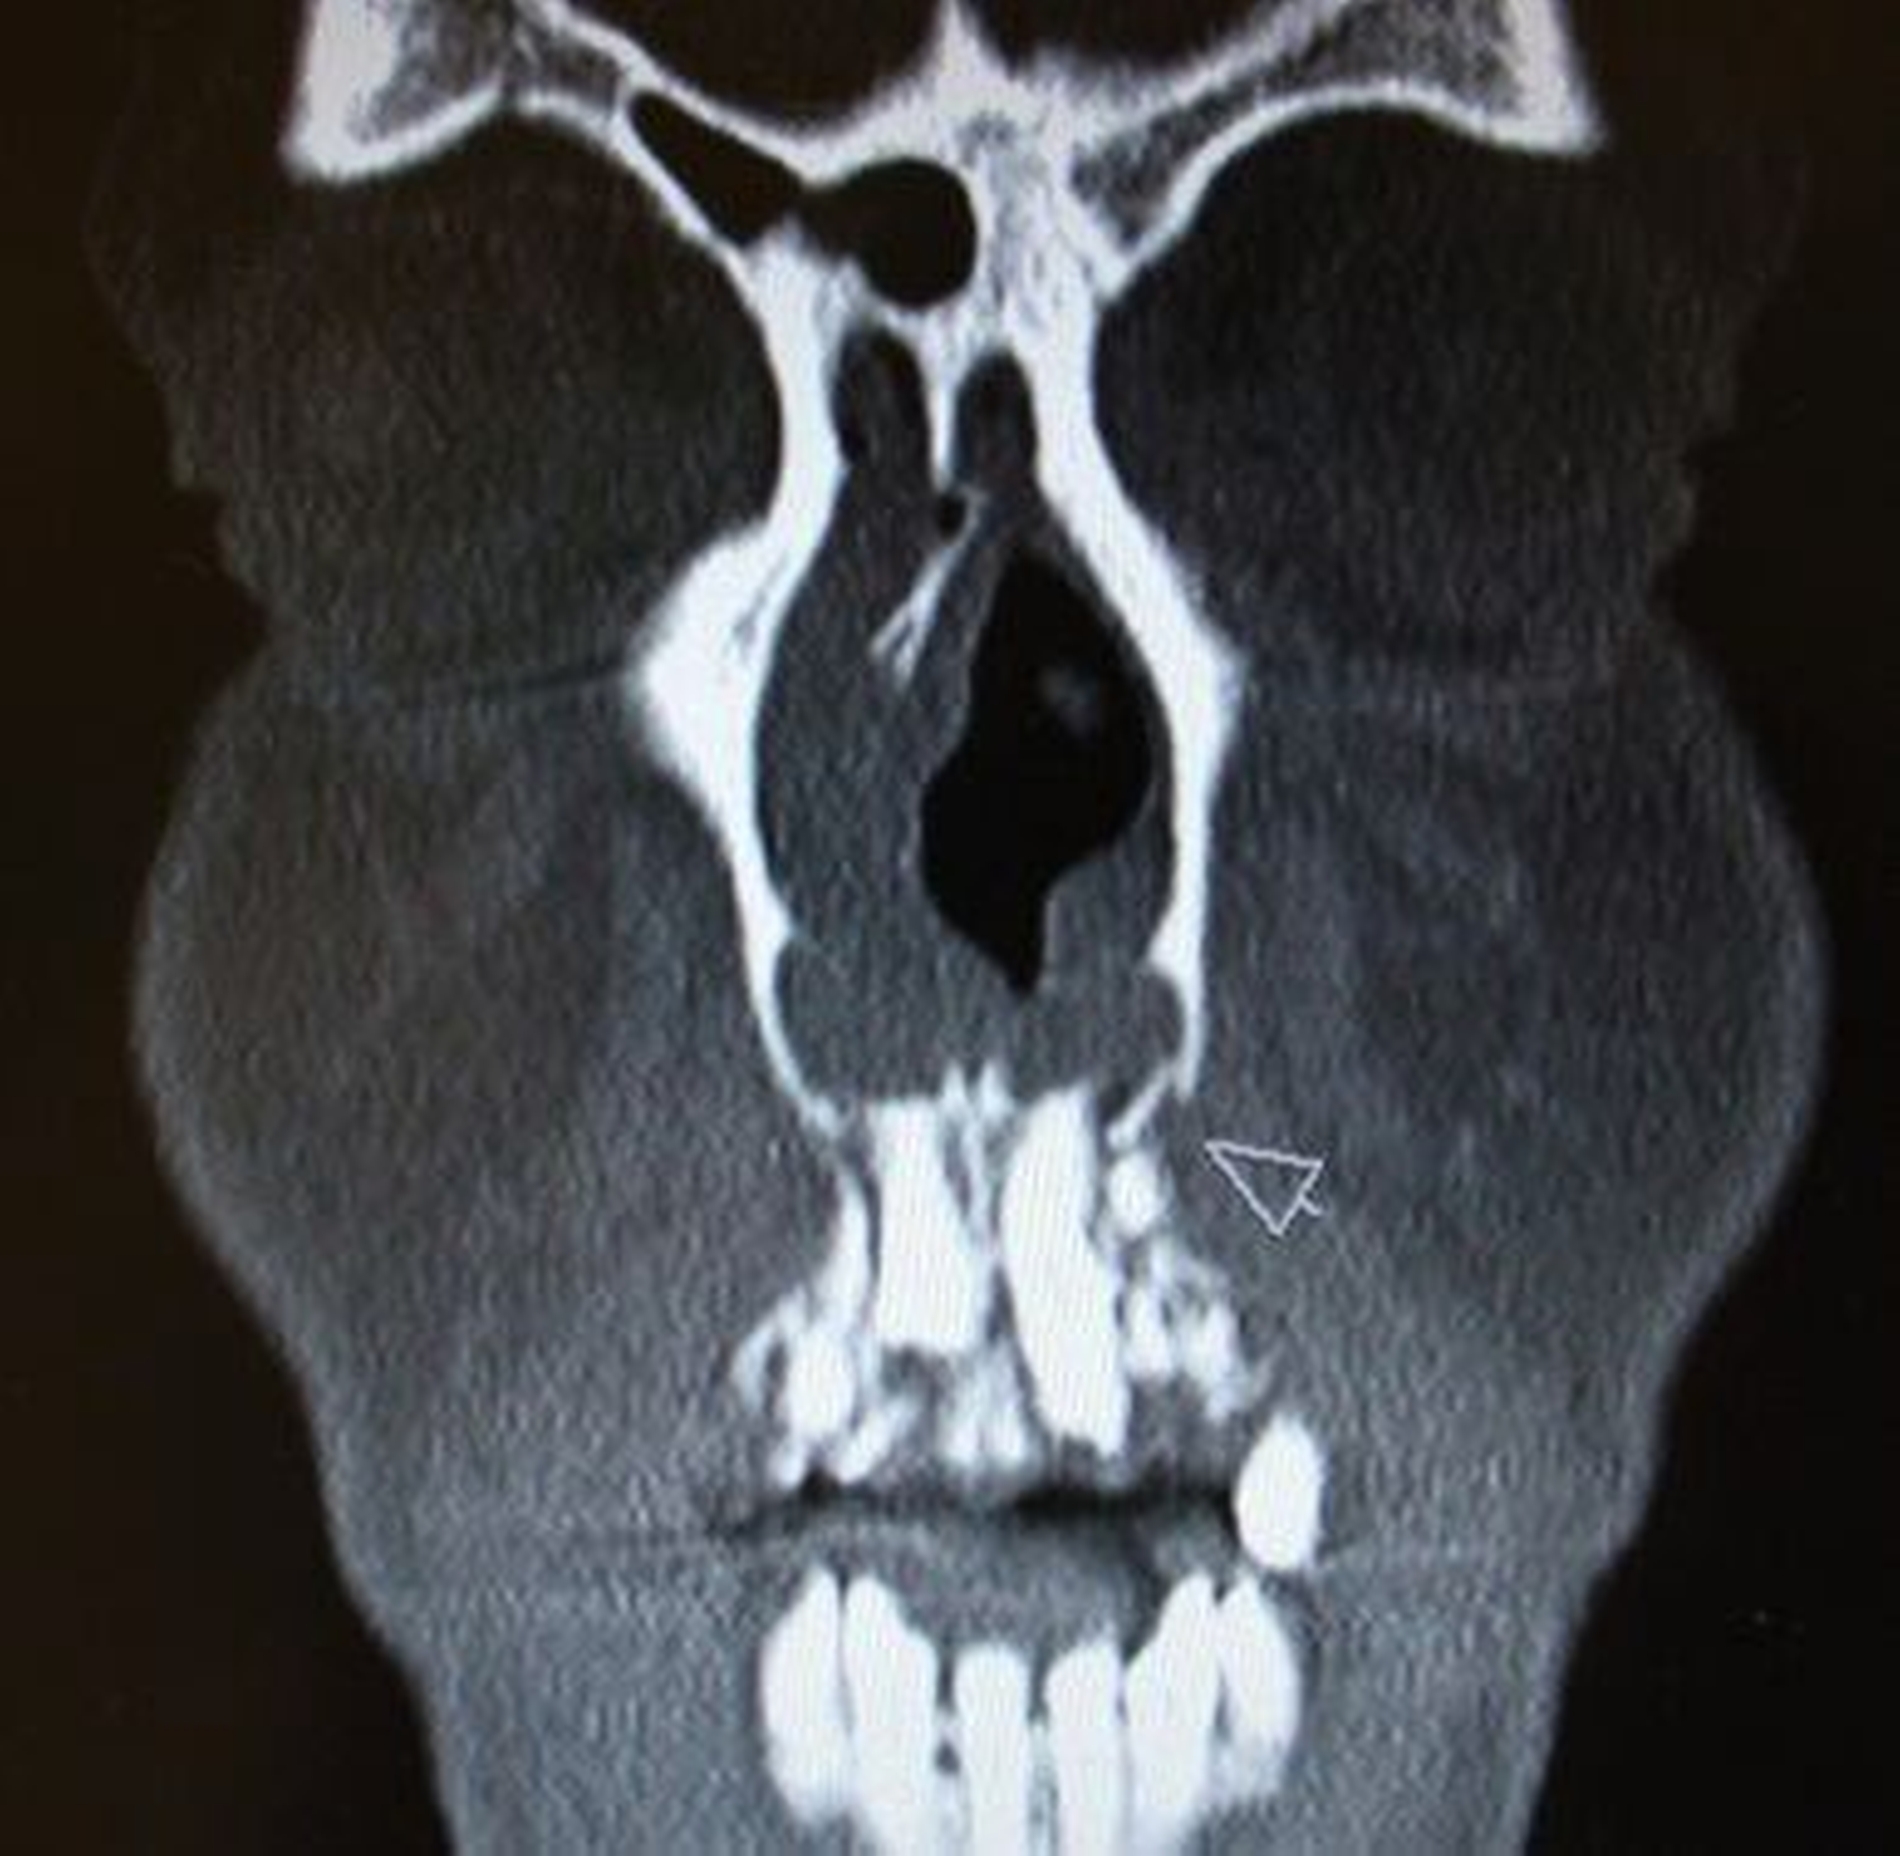

Dislokationsverletzungen von Zähnen können nicht selten mit einer Fraktur des zahntragenden Alveolarfortsatzes kombiniert sein, die auf Panoramaschichtaufnahmen oder gegebenenfalls weiterführenden Aufnahmen (Einzelzahnfilm, DVT) zur Darstellung kommen. Je nach Schweregrad wird hier zwischen einer partiellen Fraktur (Bruch der vestibulären oder oralen Alveolenwand) und einer vollständigen (Bruch der vestibulären und oralen Alveolenwand) im Sinne einer dislozierten beziehungsweise nicht dislozierten Fraktur des Alveolarfortsatzes unterschieden.

Klinisch findet sich neben häufigen, meist vertikalen Schleimhauteinrissen gegebenenfalls eine tastbare Stufenbildung (Abbildung 6). Dislozierte Alveolarfortsatzfrakturen gehen in der Regel mit einer Okklusionsstörung einher, die Sensibilität der betroffenen Zähne geht dabei häufig verloren. Die Therapie der Alveolarfortsatzfrakturen weist einige Besonderheiten auf, die in der entsprechenden Empfehlung der Leitlinie aufgeführt sind.